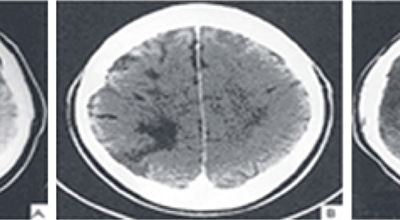

뇌경색의 경색이란 허혈성 괴사를 말해요. 여기서 허혈이란 혈관이 막히는 것을 말하고 괴사는 말 그대로 일부가 죽는 것을 말하는데 뇌경색의 경우 뇌의 혈관이 막혀 뇌세포 일부가 죽는 걸 의미해요. 뇌혈관이 막혔다 해서 혈액 공급이 안되는것은 또 아니에요.

막힌 혈관으로도 혈액이 공급되긴 하나 혈관이 막혀있어 혈액을 보내긴 하나 제대로 흐르지 못하고 혈액이 쌓이고 축적되어 물풍선에 물이 꽉 차서 터지듯 뇌혈관이 터지는 경우가 일어날 수 있는데 이를 뇌출혈 이라고 해요. 물론 외상으로 인한 뇌출혈도 있지만 이처럼 뇌경색으로 인해 혈관이 막혀 터지는 경우도 있어요.